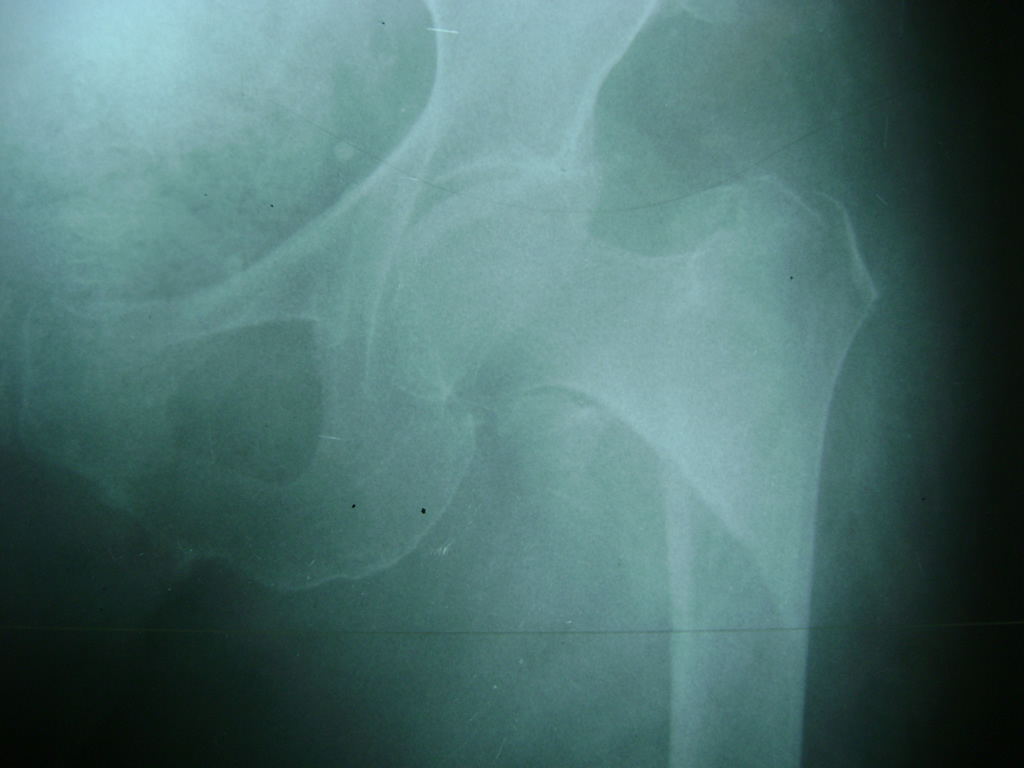

La cirugía de fractura de cadera se realiza para reparar una ruptura en la parte superior del hueso del muslo. Este hueso se denomina fémur.

Es parte de la articulación coxofemoral. Si una fractura de cadera no recibe tratamiento, es posible que deba permanecer en una silla o en la cama.